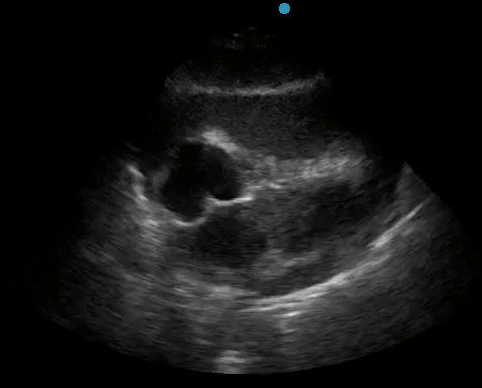

Historically, cardiac tamponade was diagnosed as a constellation of clinical findings, including Beck’s triad (hypotension, jugular venous distention, muffled heart sounds), pulsus paradoxus, and electrical alternans on electrocardiography. However, studies have demonstrated that the clinical history and physical exam perform poorly, with the sensitivity of Beck’s triad being 0% in one review.5 Furthermore, vital sign derangements are also not reliable predictors of tamponade; tachycardia was only present in 59.5% of patients, while hypotension was only present in 31.4%.5 Thus, point-of-care echocardiography should be used to confirm the presence of pericardial effusions and secure a diagnosis of tamponade. Although trivial and small effusions may be difficult to visualize, moderate to large pericardial effusions are easily identified as fluid collections surrounding the myocardium in the subxiphoid view. On parasternal long views, pericardial effusions may be visualized anterior to the right ventricular free wall and posterior to the LV, crossing in front of the descending aorta (Figure 1). While serous pericardial effusions are typically hypoechoic and readily identified as a fluid-filled space, hemorrhagic or purulent effusions may be heterogeneous and similar in appearance to a generous pericardial fat pad, although fluid motion is likely to be seen.4

Figure 1. A) Subxiphoid cardiac view, demonstrating a moderately-sized pericardial effusion. B) Parasternal Long Axis cardiac view, demonstrating a moderately-sized pericardial effusion which tracks anterior to the descending aorta.